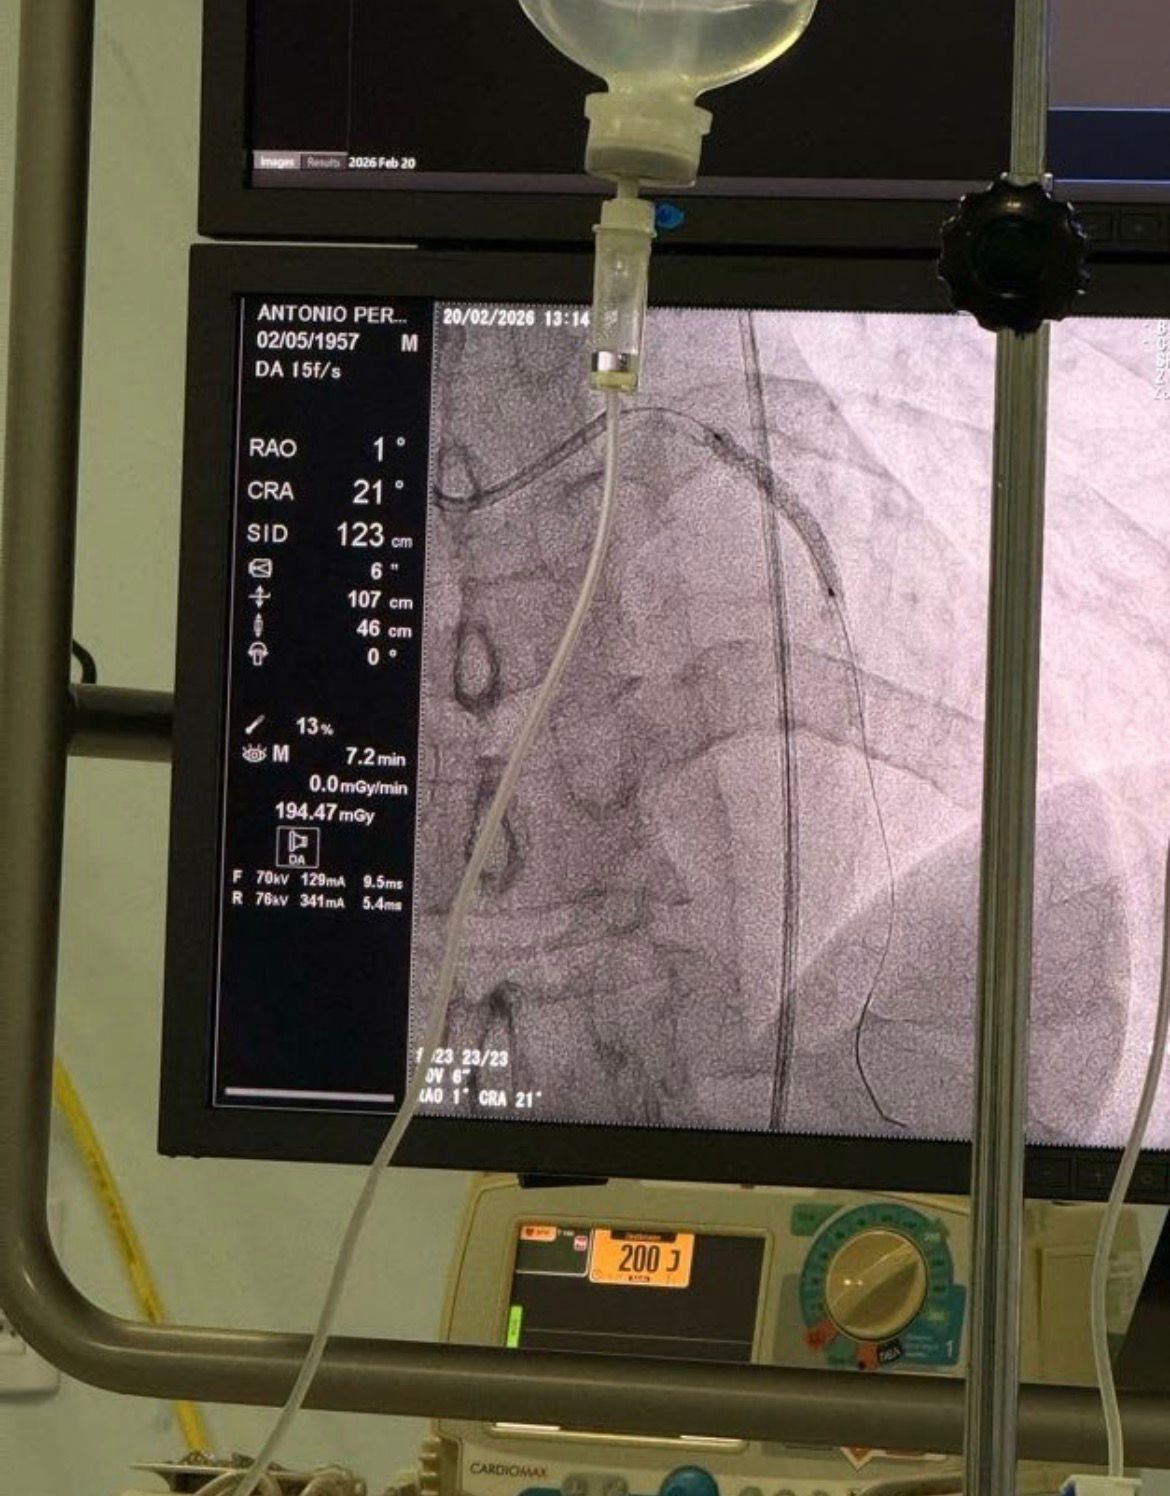

A Hemodinâmica do Complexo Hospitalar Deputado Janduhy Carneiro, em Patos, gerenciada pela Fundação Paraibana de Gestão em Saúde (PB Saúde), alcançou um marco na cardiologia sertaneja ao realizar, pela primeira vez na unidade, um procedimento de angioplastia complexa utilizando a tecnologia do Balão Farmacológico. A técnica, considerada inédita na unidade, foi crucial para o tratamento de um paciente de alto risco.

O procedimento, realizado nesta sexta-feira (20), tratou Antônio Ferreira de Almeida, de 69 anos, procedente da cidade de Jericó. O paciente, que já possuía quatro stents implantados em outro serviço, desenvolveu novas lesões nas regiões dos dispositivos. A complexidade dos vasos impedia a implantação de novos stents, tornando o tratamento ineficaz pelas vias convencionais.

"Através do uso do balão farmacológico conseguimos desobstruir os vasos com lesão com grande sucesso e salvar mais vida," afirmou o médico. Ele ressaltou que a tecnologia foi decisiva, visto que "esse paciente está internado em UTI com queixas refratárias de angina."